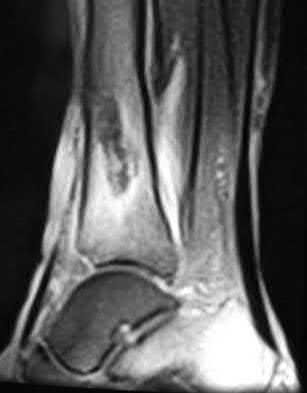

A 25-year-old female is involved in a motor vehicle collision. She presents with the isolated injury seen in Figures A through D. Her leg is swollen but her skin is intact. She has no clinical signs of compartment syndrome. Which of the following treatment options will allow for maintenance of fracture alignment and minimize the risk of soft tissue complications?

The patient presents with a closed distal third metaphyseal-diaphyseal distal tibia fracture with simple intra-articular extension. Immediate intramedullary nailing along with percutaneous fixation of the articular component provides appropriate restoration of length, rotation and alignment and minimizes the risk of wound complication.

Displaced distal third tibia fractures may be associated with simple intraarticular extension. Operative treatment of intra-articular distal tibia fractures has historically been performed with open reduction and internal fixation. Early open reduction and plate fixation of pilon fractures has been associated with high rates of infection and wound complication. In select patterns with simple articular extension, percutaneous screw fixation and medullary nailing may provide appropriate reduction with minimal soft-tissue risk.

Figures A and B demonstrate a distal third tibial shaft fracture with simple intra-articular extension. The axial and coronal CT cuts in Figures C and D further clarify the articular injury. Illustrations A and B demonstrate a comminuted distal third tibial fracture with simple intra-articular extension. Illustrations C and D are fluoroscopic images of the same injury after intramedullary nailing and percutaneous fixation of the articular component.